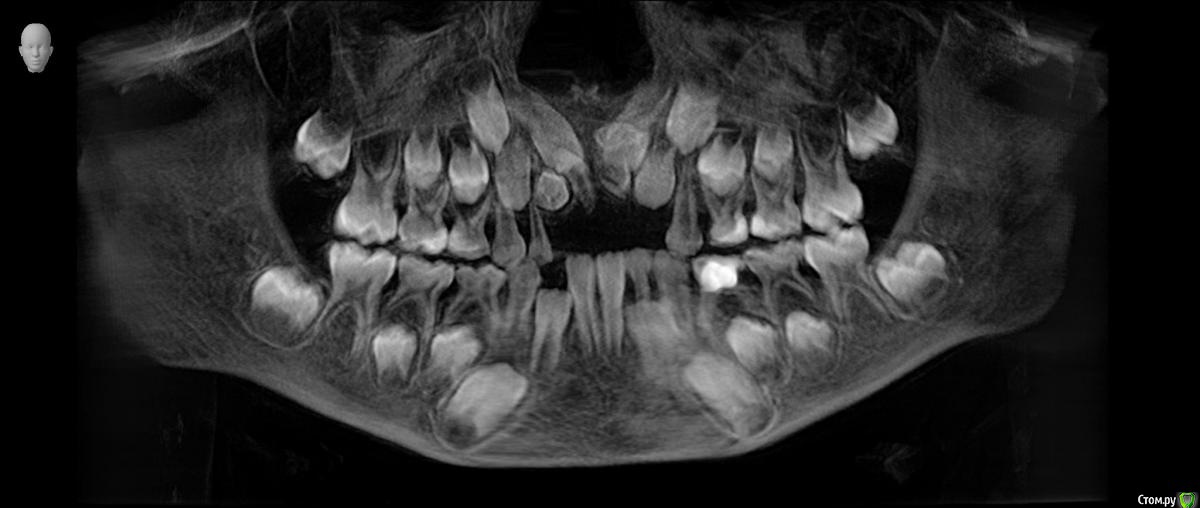

Сверхкомплект. 2 или 4? План лечения.

Ребенок 6 лет.

По теме интересует какие лишние зубы можно дождаться и удалить после прорезывания, какие требуют оперативного вмешательства, какие сроки, тот что на месте 11 не вниз корнем?

Были в 4 клиниках, случай не типичный, варианты лечения разные. От ничего не делать ждать, до резать удалять. Начинали с 2 сверхкомплектов, потом нашли еще два.